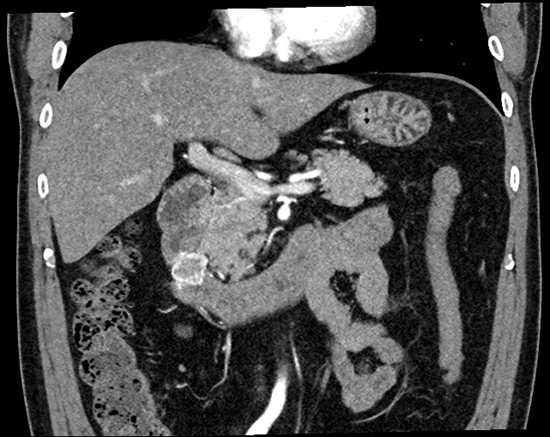

조직검사 결과 위장관기질종양(Gastrointestinal stromal tumor, GIST)으로 진단되었고 전이평가등을 위한 복부 전산화단층촬영상 28mm 크기의 조영증강이 잘 되는 종괴가 십이지장 제2부에서 확인되었으며 림프절이나 타 장기 전이 의심소견은 없었습니다. [그림2]

[그림2] 복부 전산화단층촬영상 십이지장 제2부의 조영증강이 잘 되는 종괴가 관찰됨.